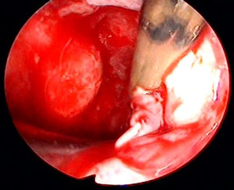

鼻腔より4mmの細径内視鏡(オリンパス社製、把持器はエンドアーム)を挿入し、下垂体腫瘍や頭蓋底腫瘍の手術を行います。

下垂体腺腫の被膜外摘出を行い、腫瘍の摘出の向上と正常下垂体機能の温存を行っています。

腫瘍摘出後:下垂体柄、視神経、内頚動脈が確認できる